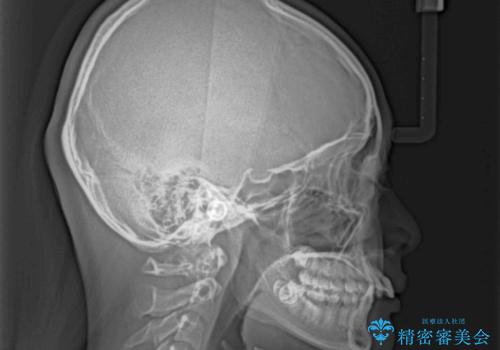

奥歯の咬み合わせを見ると、上顎が下顎に対して相対的に前方にありました。

咬み合わせも深くなっていたため、上顎臼歯を後方に移動させつつ、下顎の小臼歯を直立させ、奥歯の咬み合わせを改善する必要があります。